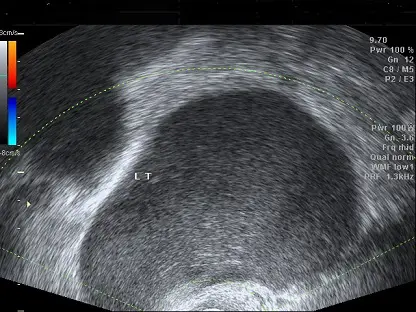

一個 30歲無性經驗女性來到門診,她主訴經痛已持續 5 年,長期使用止痛藥緩解症狀,此外她並無經血過多或頻尿之現象。她的經期剛結束,經安排婦科超音波檢查發現左側卵巢有一直徑約 8x7 公分的卵巢囊腫(如圖),下列何者為最可能的診斷?

從所提供的經陰道超音波影像可見:

- 左側卵巢有一顆約 8×7 公分的單房性囊腫。

- 囊腫內呈均質低回波(homogenous low-level echoes),俗稱 “ground glass” 外觀。

- 囊壁平滑,未見明顯隔膜、實質結節或鈣化。

- Doppler 評估不見明顯內部血流訊號。

- 周邊可見正常卵巢組織輕度壓迫(ovarian crescent sign),顯示其為良性囊性病變。

以上特徵與 endometrioma 的典型超音波表現相符,為“巧克力囊腫”內含陳舊血液所致之低回波均質質地。此影像中並無簡單囊腫之完全無回聲,也未有惡性病灶常見之複雜結構或血流。